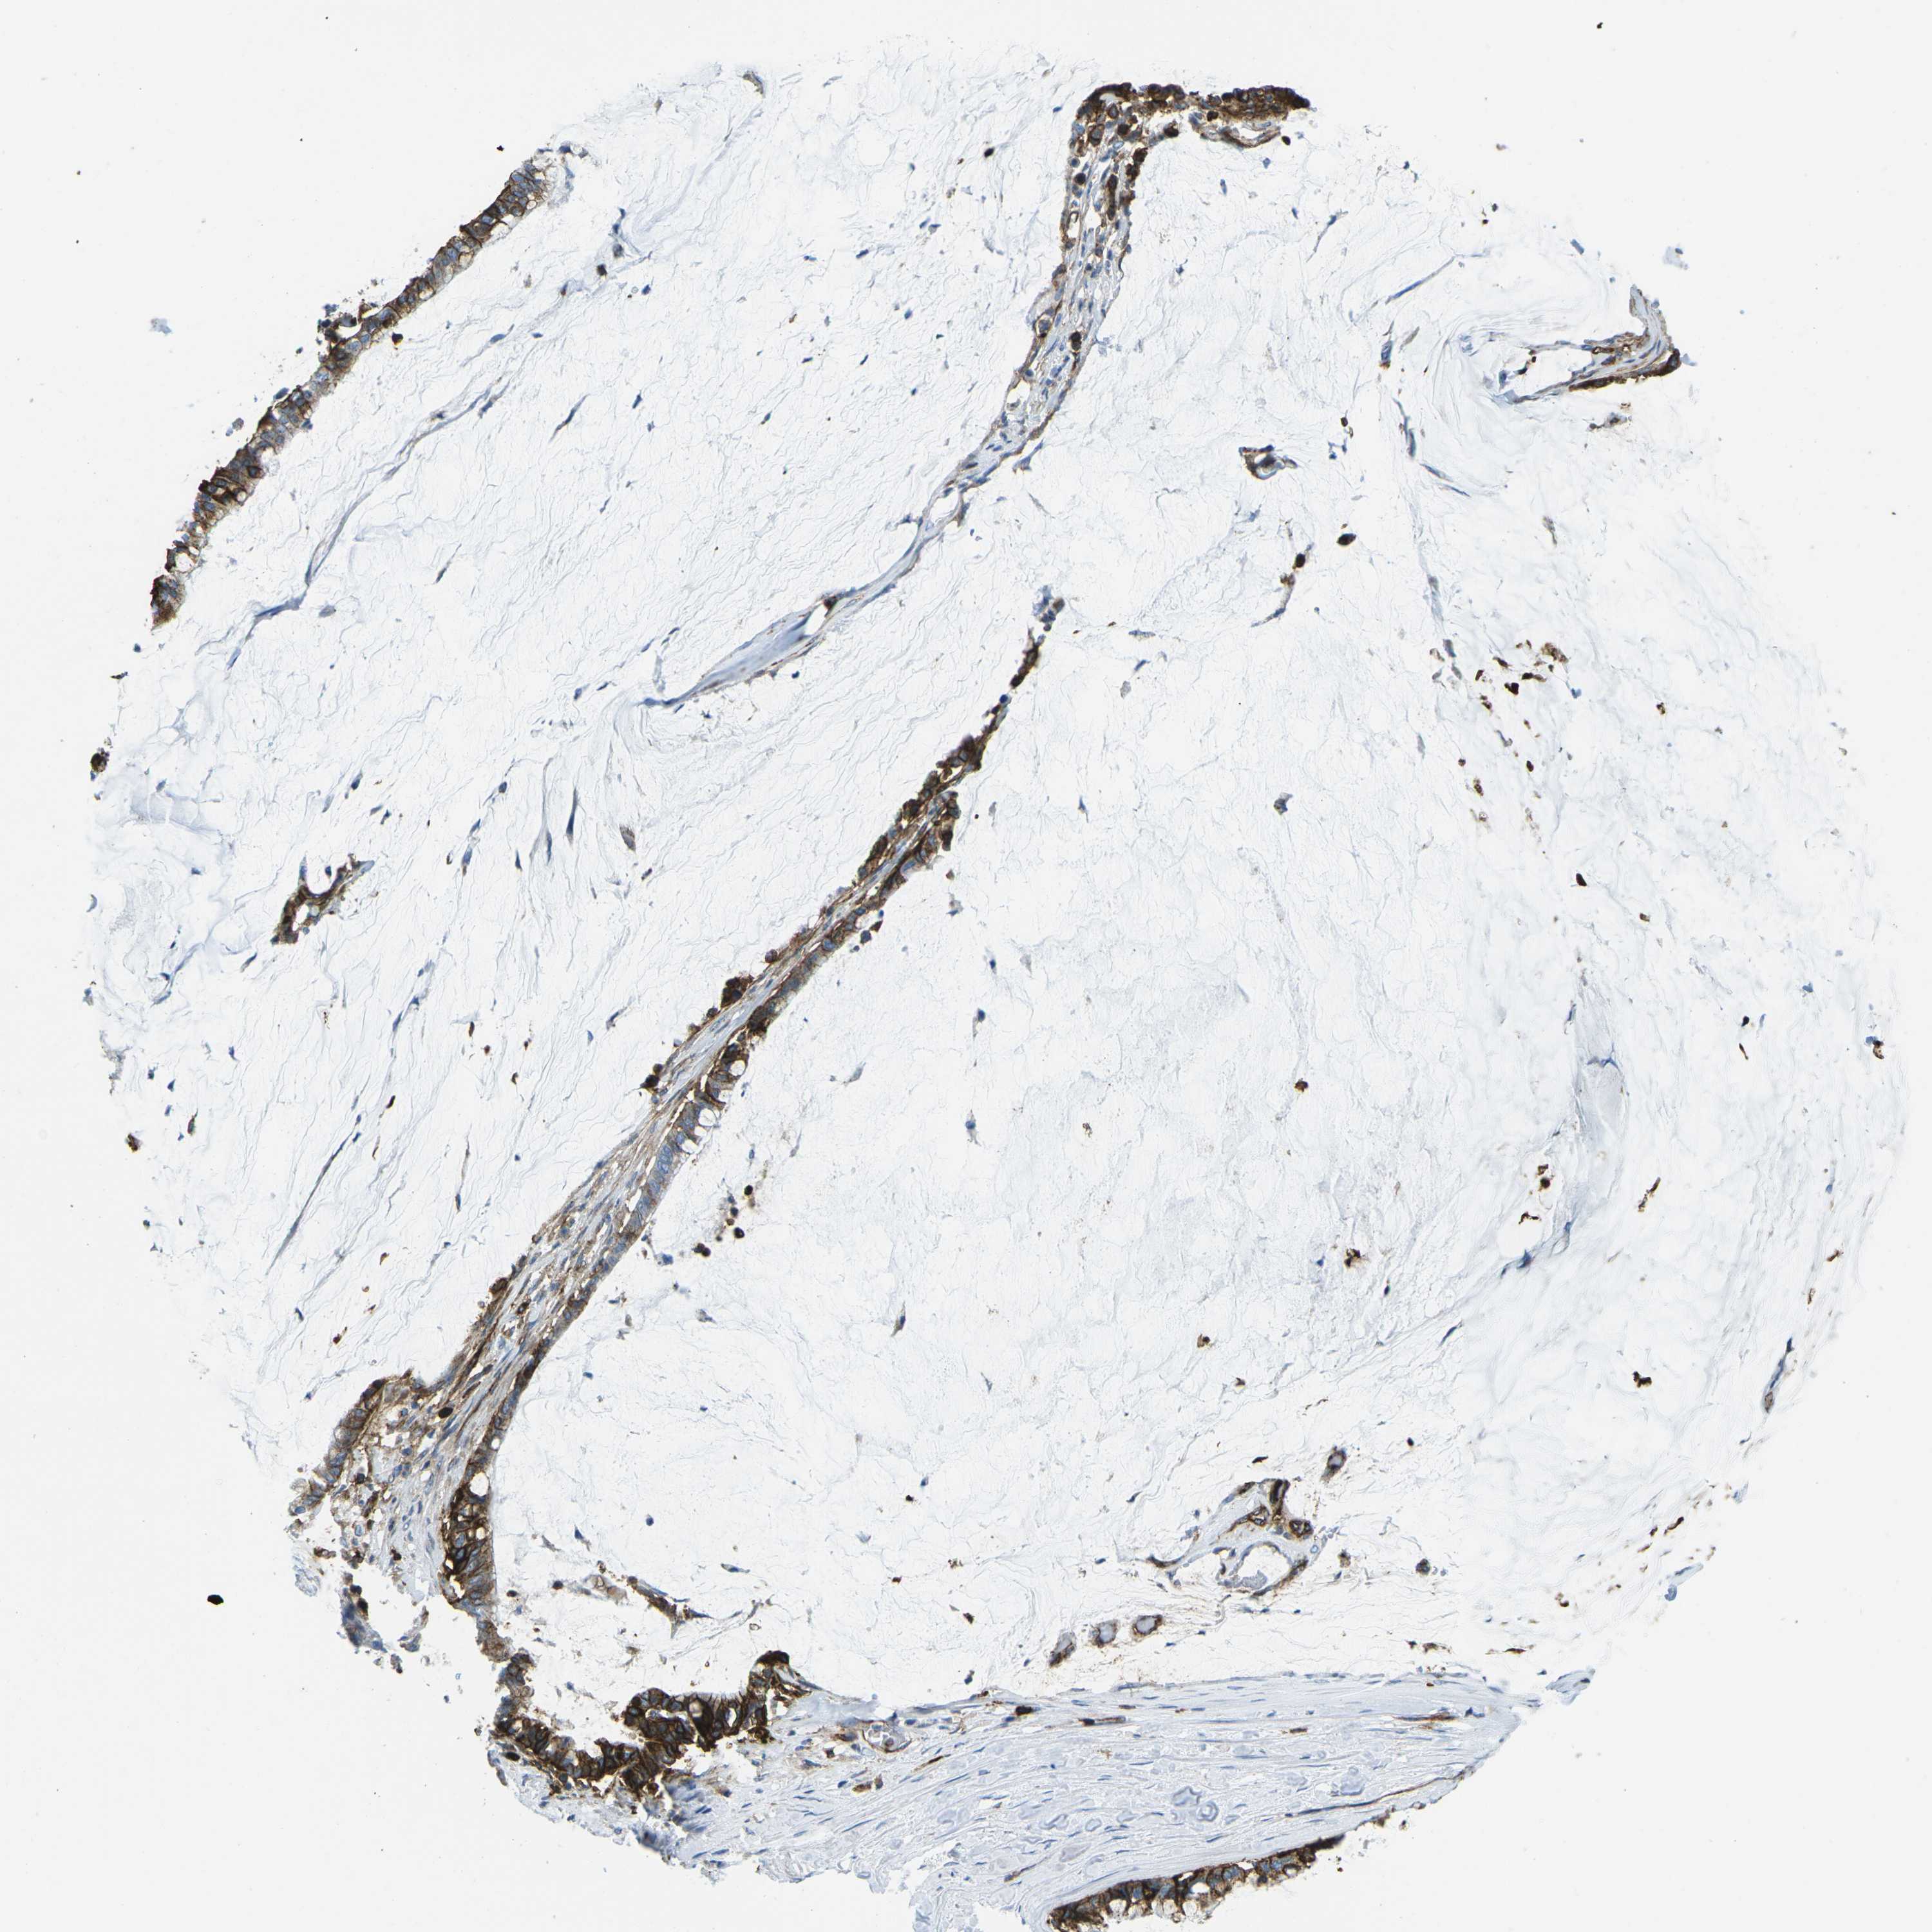

PANCREATIC CANCER - Protein expressioni

A mouse-over function shows sample information and annotation data. Click on an image to view it in a full screen mode. Samples can be filtered based on level of antibody staining by selecting one or several of the following categories: high, medium, low and not detected. The assay and annotation is described here.

Note that samples used for immunohistochemistry by the Human Protein Atlas do not correspond to samples in the TCGA dataset.

Antibody stainingi

Antibody staining in the annotated cell types in the current human tissue is reported as not detected, low, medium, or high, based on conventional immunohistochemistry profiling in selected tissues. This score is based on the combination of the staining intensity and fraction of stained cells.

Each image is clickable and will lead to virtual microscopy that enables deeper exploration of all samples and also displays staining intensity scores, fraction scores and subcellular localization as well as patient and tissue information for each sample.

Antibody CAB015418

Staining

High

Medium

Low

Not detected

Intensity

Strong

Moderate

Weak

Negative

Quantity

>75%

75%-25%

<25%

None

Location

Nuclear

Cytoplasmic/membranous

Cytoplasmic/membranous,nuclear

Adenocarcinoma, NOS